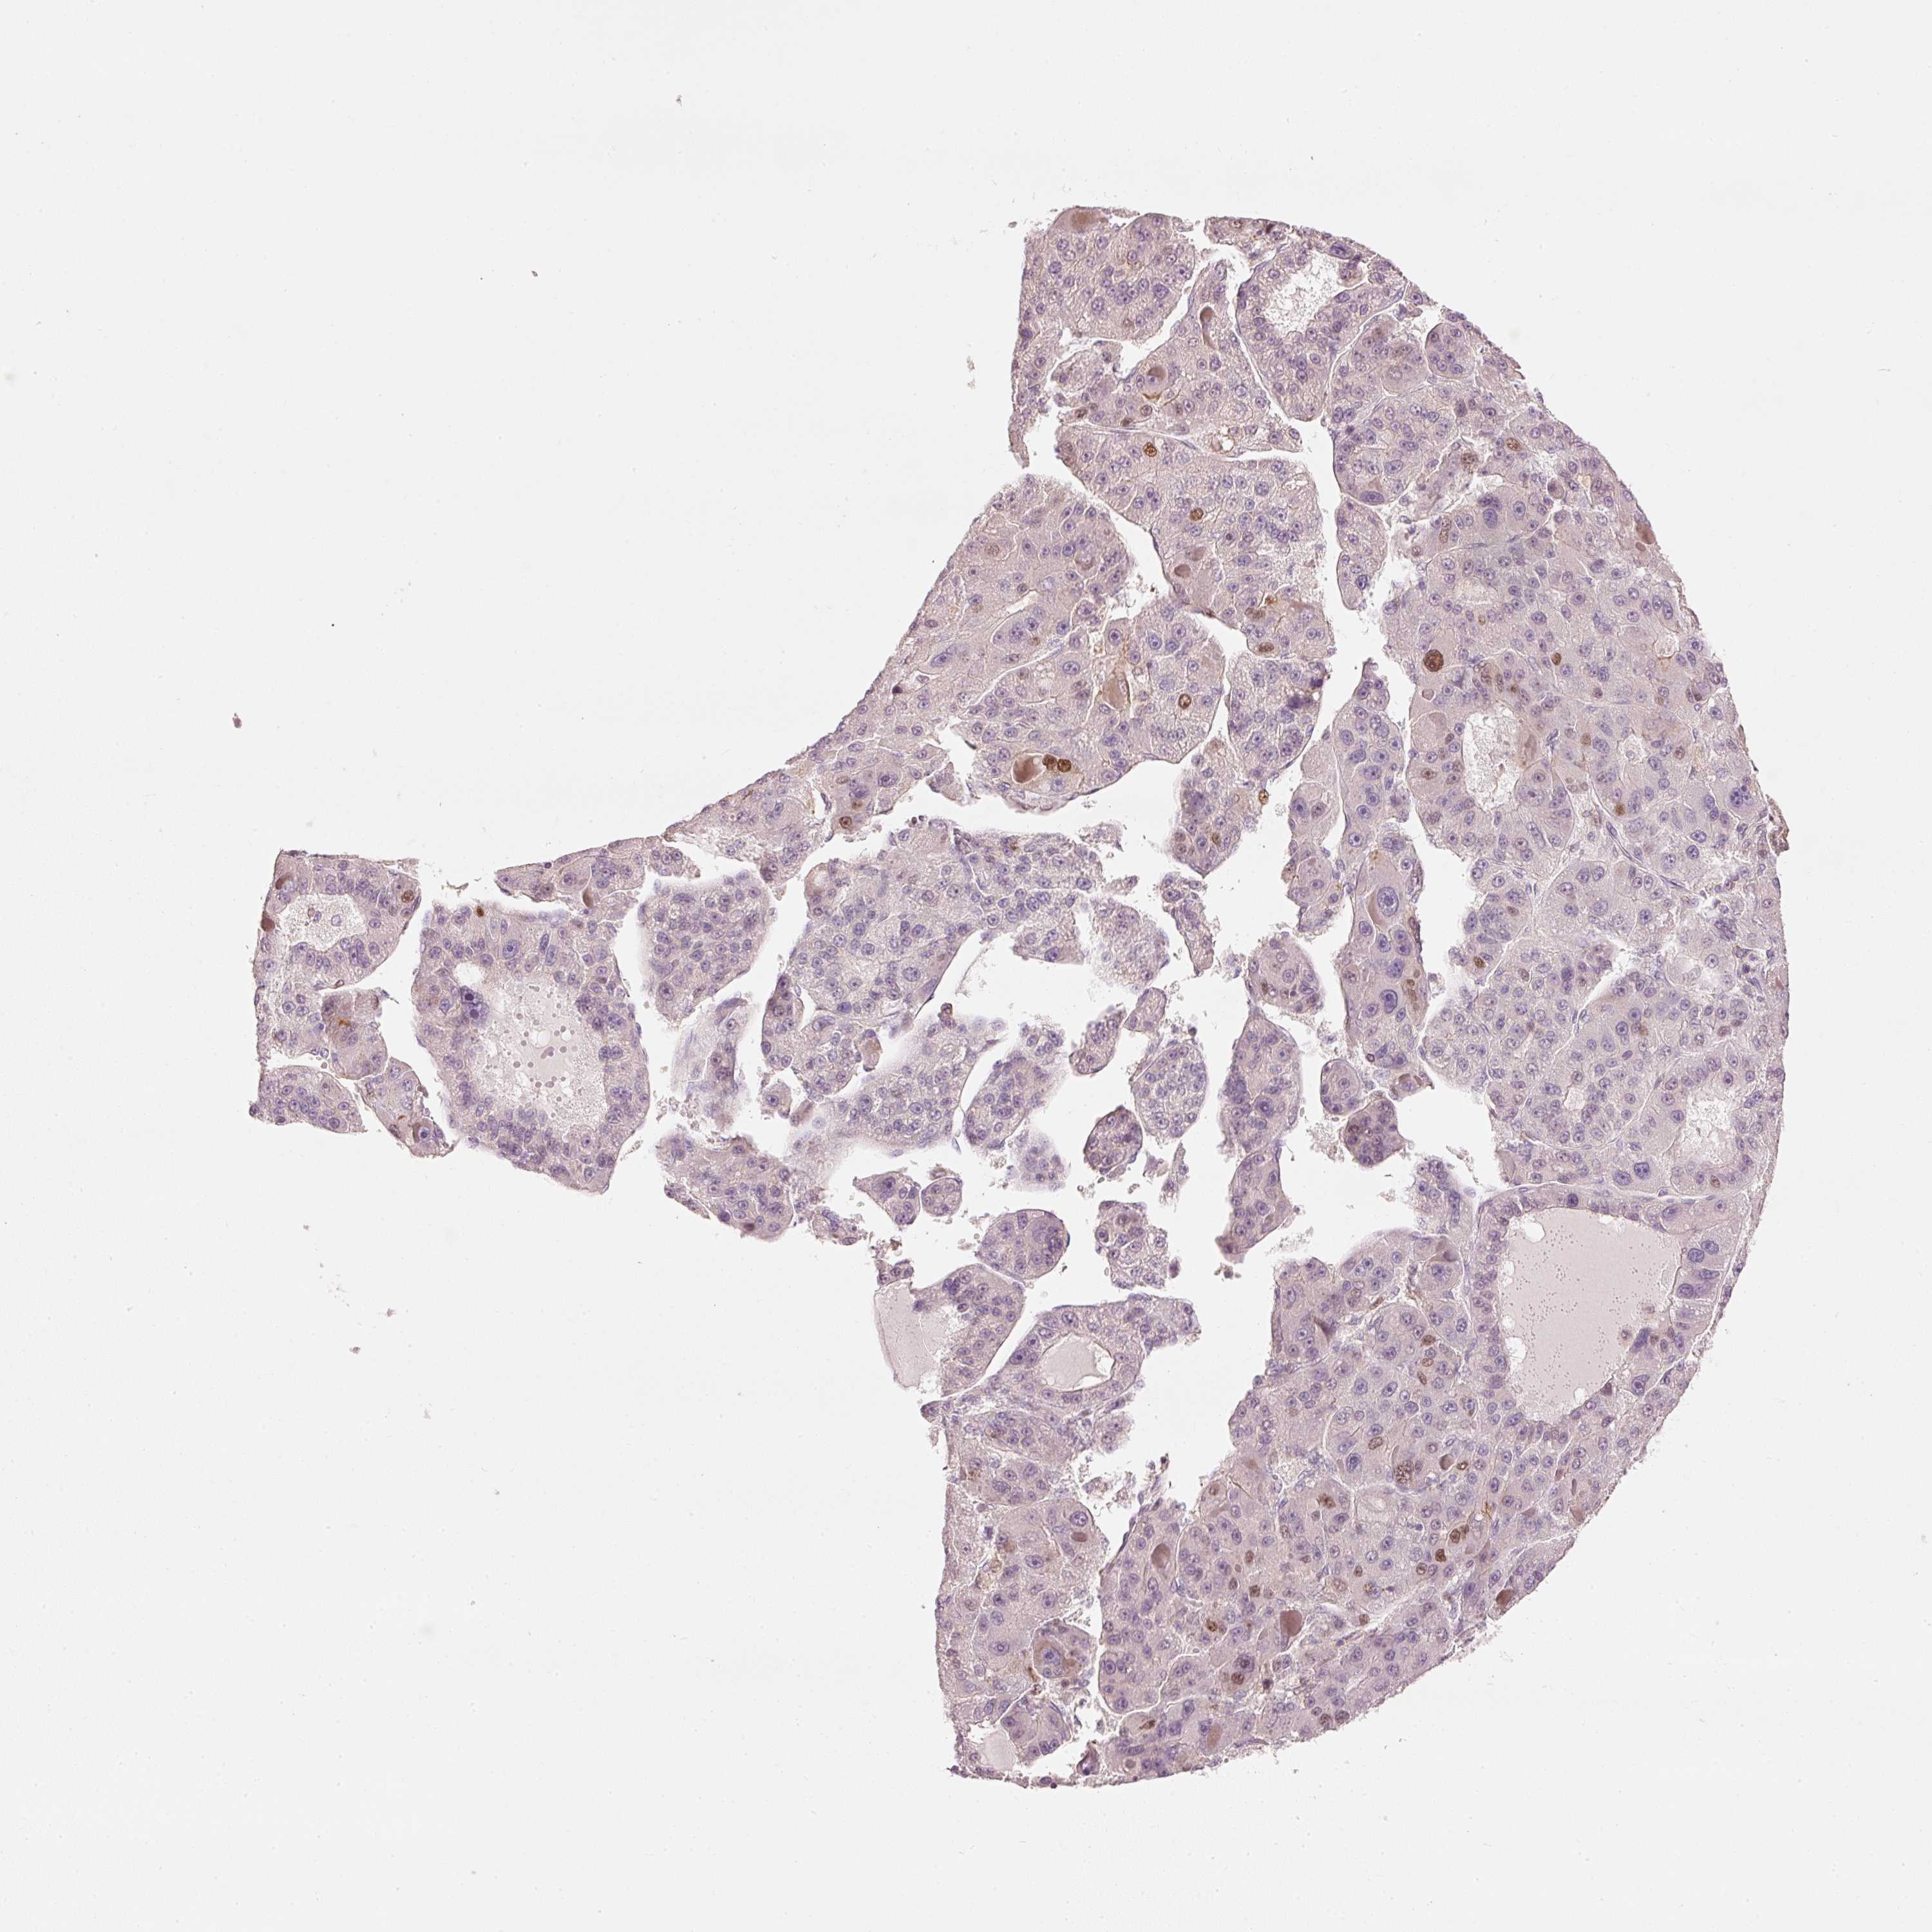

LIVER CANCER - Protein expressioni

A mouse-over function shows sample information and annotation data. Click on an image to view it in a full screen mode. Samples can be filtered based on level of antibody staining by selecting one or several of the following categories: high, medium, low and not detected. The assay and annotation is described here.

Note that samples used for immunohistochemistry by the Human Protein Atlas do not correspond to samples in the TCGA dataset.

Antibody stainingi

Antibody staining in the annotated cell types in the current human tissue is reported as not detected, low, medium, or high, based on conventional immunohistochemistry profiling in selected tissues. This score is based on the combination of the staining intensity and fraction of stained cells.

Each image is clickable and will lead to virtual microscopy that enables deeper exploration of all samples and also displays staining intensity scores, fraction scores and subcellular localization as well as patient and tissue information for each sample.

Antibody HPA054060

Staining

High

Medium

Low

Not detected

Intensity

Strong

Moderate

Weak

Negative

Quantity

>75%

75%-25%

<25%

None

Location

Nuclear

Cytoplasmic/membranous

Cytoplasmic/membranous,nuclear

Cholangiocarcinoma

Carcinoma, Hepatocellular, NOS